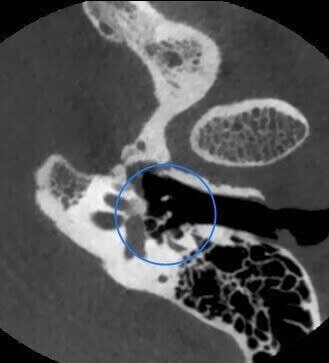

Newtom VGi evo ofrece una gama completa de FOV para la adquisición de volúmenes 3D nítidos y detallados, por lo que se adapta a cualquier necesidad clínica. La selección del campo de vista permite optimizar la región anatómica analizada garantizando un imaging de alta calidad con la mínima dosis posible.

En las exploraciones más avanzadas, los modos Boosted y Enhanced ofrecen la posibilidad de obtener imágenes con el máximo nivel de detalle y calidad, sin concesiones. Disponible para FOV de hasta 15x5 cm, el modo HiRes es ideal para el estudio de áreas anatómicas circunscritas con altísima definición.

El software NNT - Medical Suite ofrece una interfaz intuitiva y avanzada para efectuar, procesar y compartir exámenes 2D y 3D que mejora la gestión de las imágenes con instrumentos avanzados para la planificación de los tratamientos de implantología, endodoncia, periodoncia, cirugía maxilofacial y radiología. Un ecosistema integrado para una gestión diagnóstica de vanguardia.